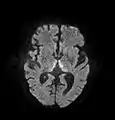

The most common application of conventional DWI (without DTI) is in acute brain ischemia. DWI directly visualizes the ischemic necrosis in cerebral infarction in the form of a cytotoxic edema,[18] appearing as a high DWI signal within minutes of arterial occlusion.[19] With perfusion MRI detecting both the infarcted core and the salvageable penumbra, the latter can be quantified by DWI and perfusion MRI.[20]

DWI showing restricted diffusion in the mesial dorsal thalami consistent with Wernicke encephalopathy